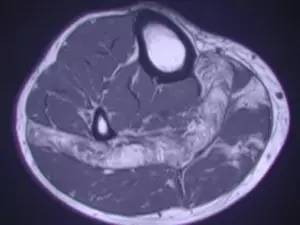

辅检:MRI、X线片、超声等。

B超或核磁共振(MRI)检查,可以明确损伤位置。